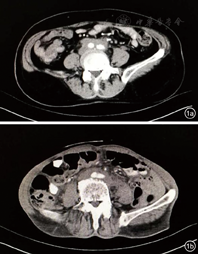

患者,女性,70岁,因"腹痛1个月"入院。患者1个月前出现全腹痛、腹胀,无发热,无恶心、呕吐,无尿频、尿急等不适。既往胃溃疡病史3年。入院后查血常规、凝血功能正常,肝肾功、电解质正常;肿瘤标志物正常;抗核抗体谱正常;免疫球蛋白A、M、G正常。胃镜检查示浅表性胃炎,肠镜检查未见明显异常。腹盆腔CT示腹主动脉及双侧髂动脉周围软组织影,考虑腹膜后纤维化(图1a)。诊断:腹膜后纤维化。患者于上级医院接受进一步治疗。电话随访患者用激素治疗后症状好转。

患者,男性,70岁,因"间断腹痛3个月"入院。患者3个月前无明显诱因出现下腹部疼痛,伴尿频,无发热,无恶心、呕吐等。既往肾炎病史10余年,曾服用激素治疗,近3年未服药。股骨头置换术后3个月。入院后血常规示血红蛋白105 g/L;红细胞沉降率46 mm/h;凝血功能正常,肝肾功、电解质正常;肿瘤标志物正常;抗核抗体谱正常;免疫球蛋白A、M、G正常。胃镜示浅表性胃炎伴糜烂,食管炎;肠镜示结肠息肉、结肠黑变病。腹部CT示右肾动脉水平至左右髂动脉分叉处可见软组织包绕,符合腹膜后纤维化CT表现(图1b)。诊断:腹膜后纤维化。患者家属拒绝穿刺活检明确病理性质。予以泼尼松口服治疗后随访患者腹痛较前好转。

本组2例患者均为老年患者,因腹痛就诊于消化内科,临床表现、实验室检查均不典型,易误诊、漏诊;其腹部CT表现均十分典型,于腹主动脉、髂动脉、肾动脉周围可见软组织包绕,但该2例患者均缺少病理学支持。故对于发生腹痛的老年患者,胃肠镜检查后不能解释患者腹痛症状,需完善腹盆腔CT或者MR以排除RPF。